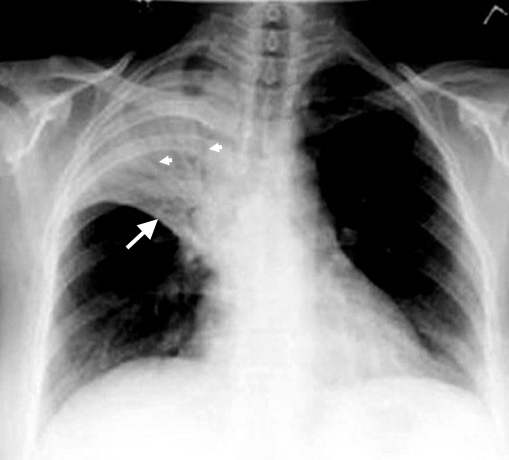

Anticipated findings in CXR in a patient with pneumococcal pneumonia |

1. Lobar density (RUL Consolidation)

- Lobar consolidation is characteristic for pneumococcal, mycoplasma and legionella pneumonia. There are many other patterns of pneumonia based on the etiological agent, ranging from broncho-pneumonia, necrotizing pneumonia, diffuse aleveolar pneumonia, interstitial pneumonia etc.

2. No significant loss of lung volume (White arrows pointing to transverse fissure)

- Alveoli are filled with inflammatory exudate, hence the volume of lung expands slightly and remains close to normal size even at the stage of resolution.